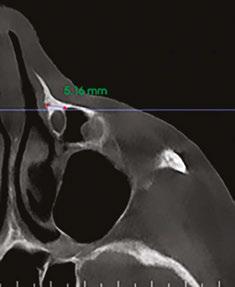

A recent 2025 retrospective review by Holtzclaw, et al.,11 evaluated anonymized cone beam computer tomography (CBCT) scans from 300 sequential referrals using PLACATE guidelines to determine transnasal dental implant feasibility. In this study, inferior conchae were initially located in the coronal plane, and imaging crosshairs were positioned just superior to this structure in the axial plane. To evaluate the ipsilateral and contralateral transnasal engagement points, imaging crosshairs were next positioned over each concha in the sagittal plane. This prelacrimal engagement point, sometimes referred to as the “Z-Point”,6,12 was then evaluated according to PLACATE guidelines as follows:

1. Simmen classification19 determined by measurement from the external aspect of the frontal maxilla to the most anterior aspect of the nasolacrimal canal (Figure 5)

2. Mediolateral measurement of prelacrimal bone width (Figure 6)

Figure 5 (left): CBCT slice (axial view) to determine Simmen classification.

Figure 6 (right): CBCT slice (axial view) for mediolateral measurement of prelacrimal bone width